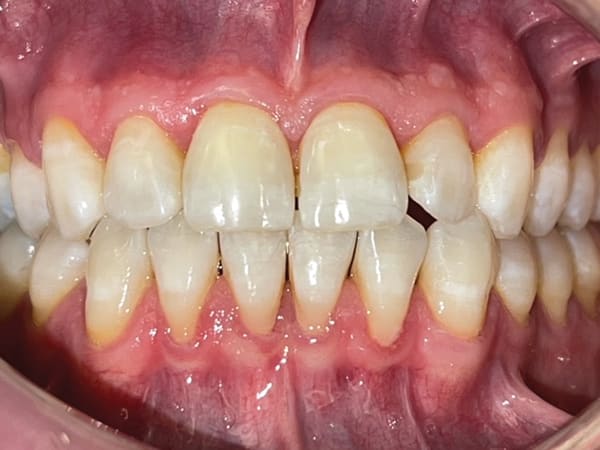

A 43-year-old male patient with good oral hygiene desired to have residual spacing closed and to stop further shifting of his teeth. The patient was a classic relapse case as a result of losing his retainers following previous orthodontic treatment. He searched online for a convenient clear aligner solution and considered SmileDirectClub (SDC) as an option. During his visit to an SDC partner office, initial photographs were taken that showed mild malocclusion and mild gingival recession in the anterior region (Figure 8). The patient complained of mandibular anterior arch rotations and interproximal spacing that was leading to continued food entrapment, specifically at the distal aspect of tooth No. 23 (Figure 9 and Figure 10). The lower anterior soft tissue presented with slight gingival dehiscence, specifically teeth Nos. 23 through 26 (Figure 10). Radiographs of the patient that had been recorded previously, which the office now had, showed stable hard-tissue condition (Figure 11). The maxillary anterior arch showed lateral incisor rotations of less than 5 degrees and limited interproximal spacing (Figure 12). The patient was periodontally classified as class II.

Left untreated, the patient's condition could lead to a poor prognosis with the possible need for soft-tissue grafting, mobility of teeth, and the potential for traumatic occlusion leading to the loss of the alveolar process. With less than 3 mm of interproximal mandibular anterior arch spacing and tooth rotations less than 15 degrees, this case was considered a mild clear aligner case with the patient being an ideal candidate for the hybrid aligner model to correct the malocclusions-specifically, the anterior malocclusions, followed by retention. During the hybrid aligner treatment process, the patient maintained his check-ups with the partner office for overall oral health and also maintained telehealth check-ins with SDC's aligner-treating doctor to ensure aligner tracking and evaluate tooth movement progress, to ensure a favorable aligner outcome.